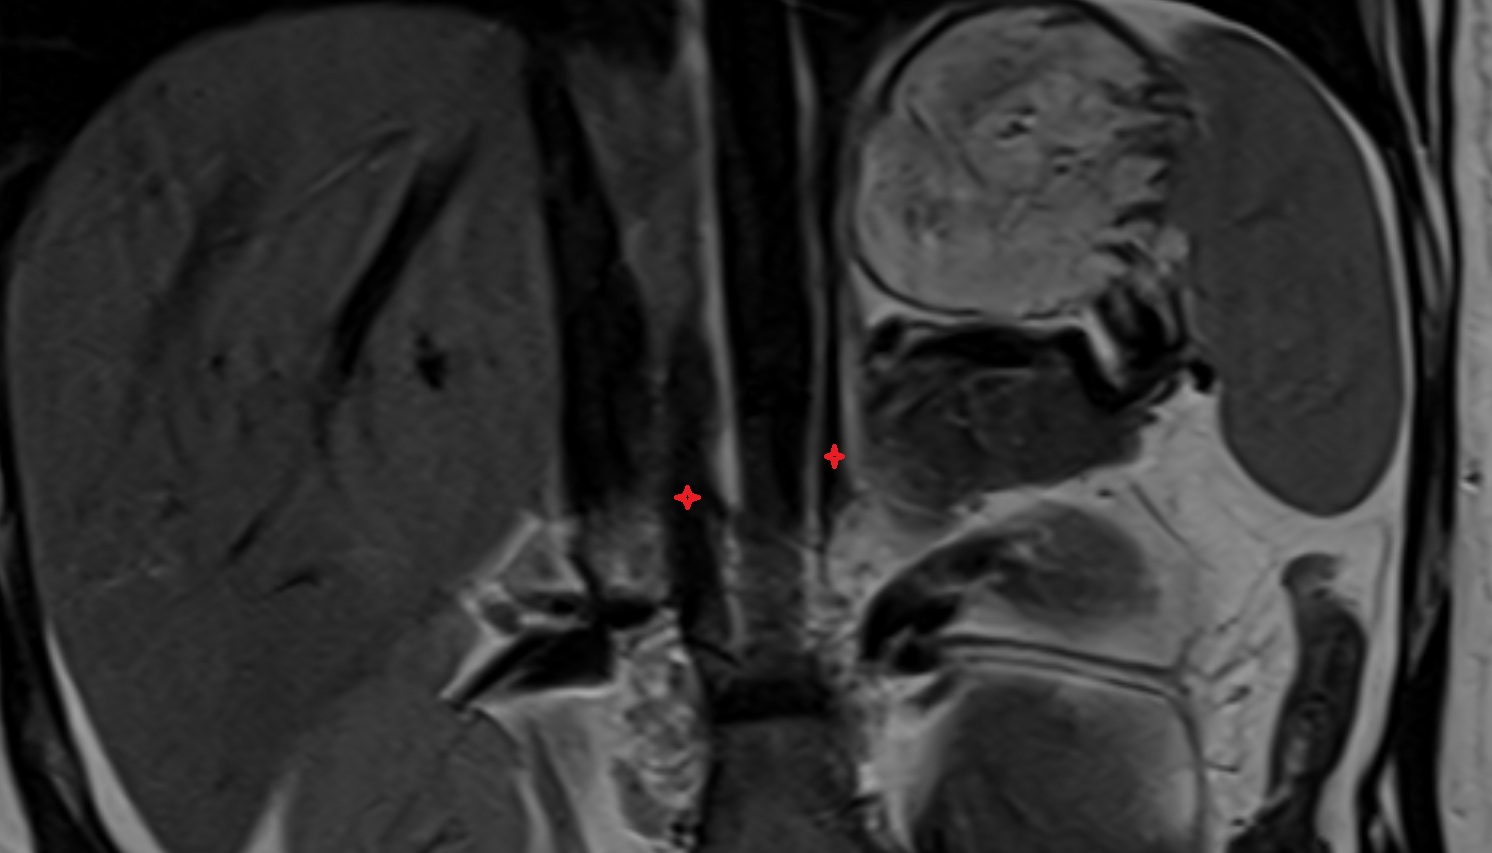

- kidneys

- Right kidney

- Left kidney

- Renal artery

- Renal vein

- Renal pelvis